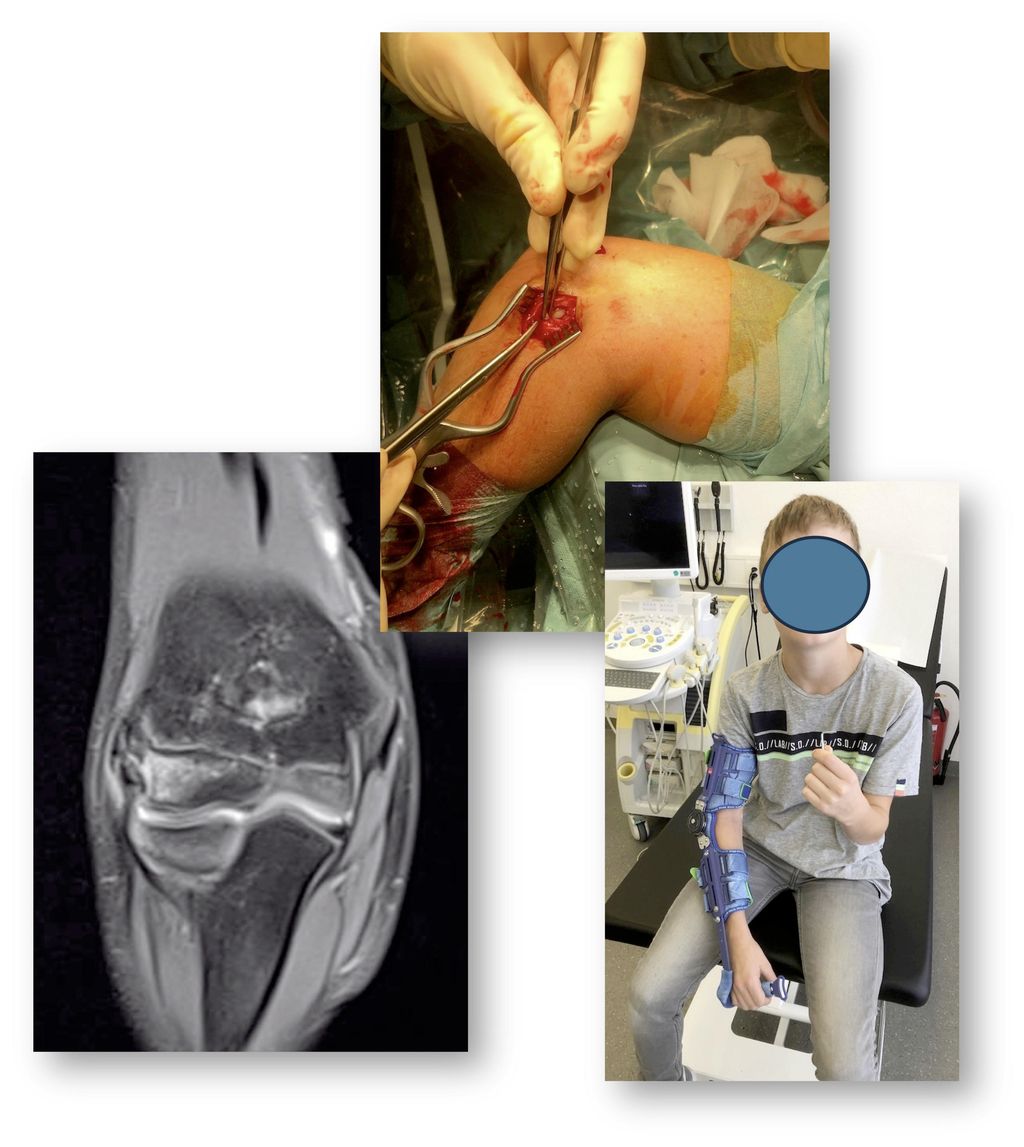

Glenohumerale Instabilität – Manschette

Auch im Kindesalter kann es Rupturen der Rotatorenmanschette geben, oft sind dies aber osteochondrale Übergangsfrakturen beziehungsweise Avulsionen. Je höher der knorpelige Anteil, desto eher wird das Problem auf dem nativen Röntgen übersehen und erst im MRI sichtbar. Daher macht ein solches bei anhaltenden Beschwerden und Dysfunktion (>3 Wochen) nach einem Sturz auch Sinn. Bei der positiven Diagnose ist eine Manschettennaht indiziert, diese muss aber unter Beachtung der Wachstumsfuge und des typischerweise sehr weichen Knochens im Humeruskopf des Kindes durchgeführt werden (Abb. 6).

Abb. 6: Avulsion des Subscapularis inklusive des cartilaginären Tuberculum minus (rote Pfeile)